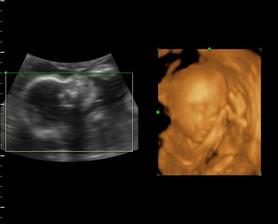

Naša Emilly

Zaciname 39tt, termin mame 23.10.09, uvidime, kedy sa malej bude chciet ist na svet a vidiet svojich rodicov. Sice sme mali neplanovane tehotenstvo, ale o to viac nas to potesilo a na malu sa nesmierne obaja tesime..je to u nas prve vnucatko, tak to bude lasky a lasky, ale tej dame aj druhemu aj tretiemu babu, uvidime, kolko nam ich zivot da. I ked mamina este studuje, urcite to zvladneme..